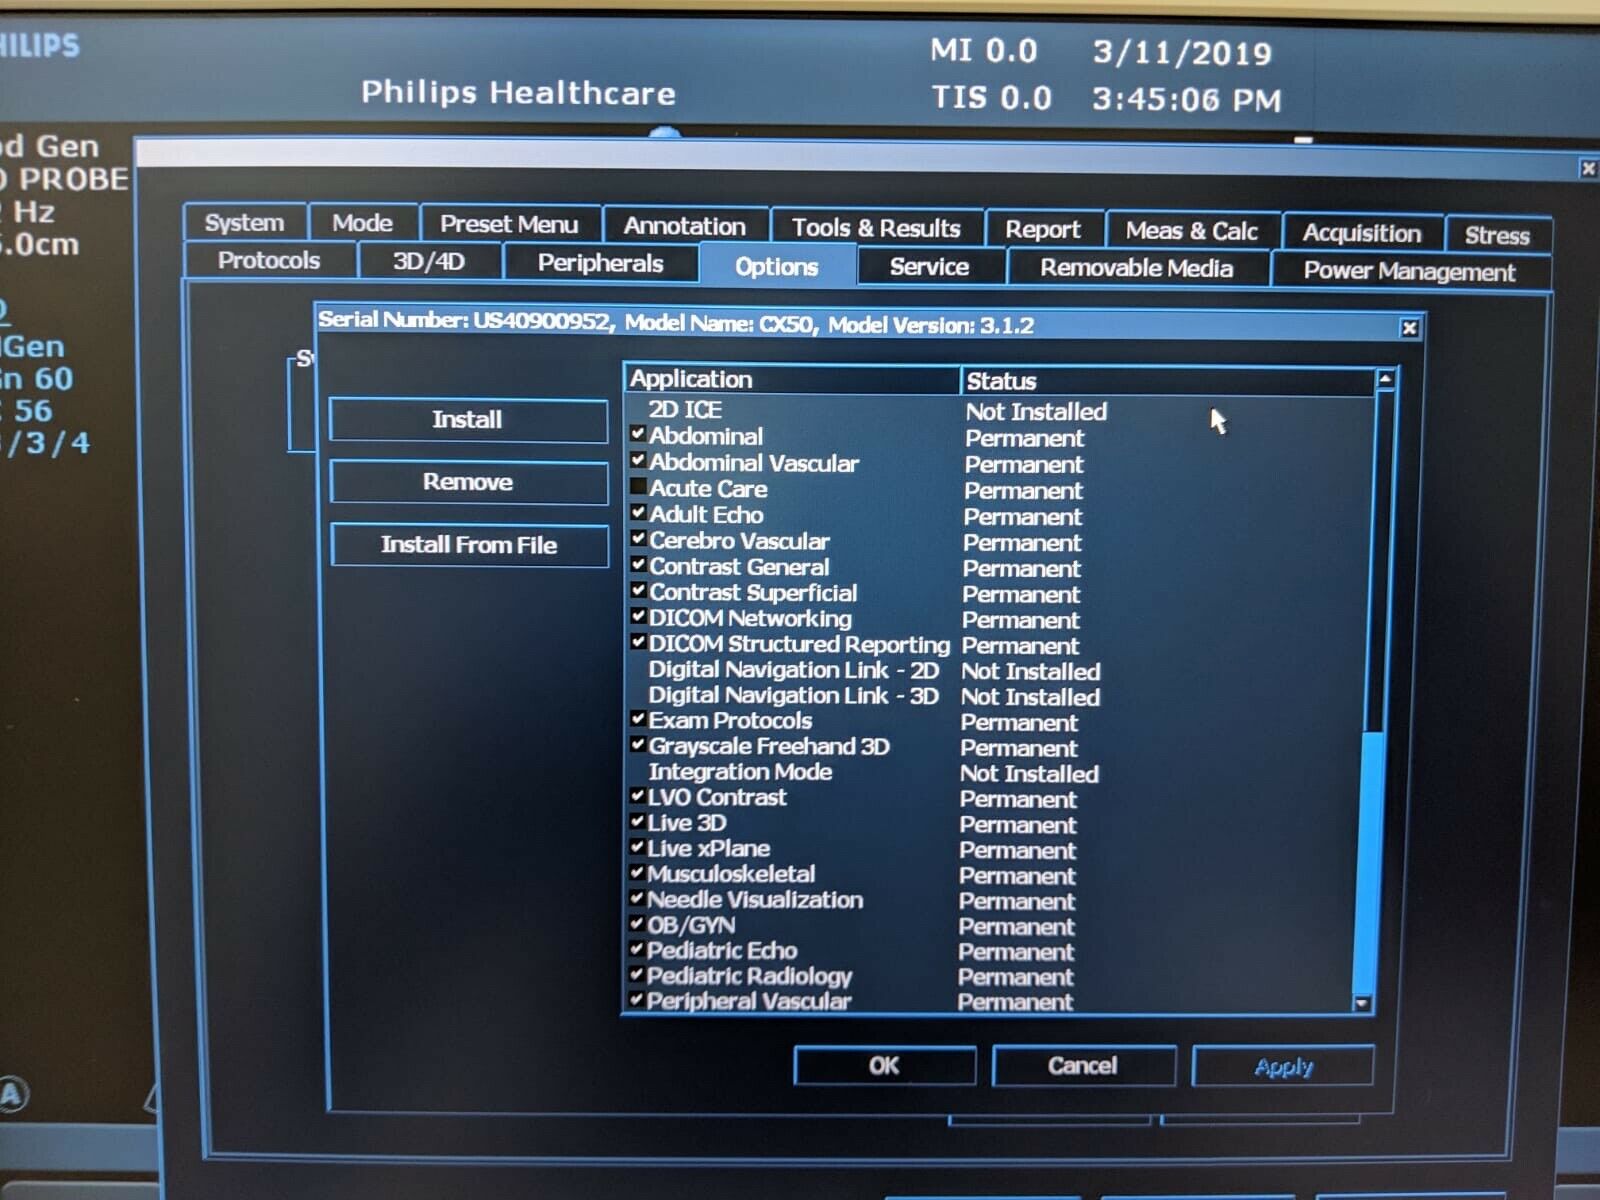

The Philips CX50 2013 Rev 4 Portable Ultrasound System with three probes is a high-performance imaging solution designed for flexibility across a range of clinical applications. This compact, portable ultrasound machine delivers premium imaging quality, making it ideal for point-of-care, cardiology, vascular, and emergency medicine. Equipped with Philips’ advanced imaging technologies like PureWave crystal technology, the CX50 provides exceptional resolution and detail, even in difficult-to-image patients.

The three included probes offer versatility, allowing clinicians to perform various exams, from cardiac and vascular to abdominal and superficial imaging. Its portability and lightweight design make it easy to transport between departments or use in field settings, without compromising on diagnostic accuracy. The CX50’s intuitive interface and customizable presets streamline workflows, making it user-friendly for fast-paced environments. This system is an excellent choice for healthcare providers needing a portable ultrasound solution that offers advanced imaging capabilities and multi-specialty support.